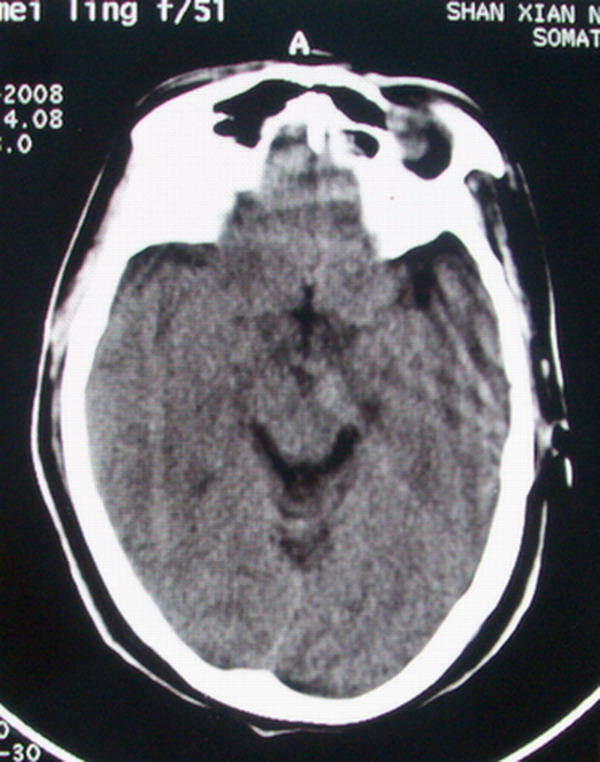

标题: CT13599:大家看是正常还是软化灶?已经重新上传 [打印本页]

标题: CT13599:大家看是正常还是软化灶?已经重新上传

手机在屏幕上拍的,不太清楚.如果需要我重新拍.

正常,枕角

正常,侧脑室后角。